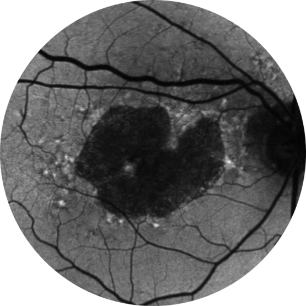

Fundus photograph of a healthy eye

Fundus photograph of an eye with geographic atrophy

GA is characterised by an irreversible and progressive loss of retinal cells and the underlying retinal structure, including photoreceptors, retinal pigment epithelium and the underlying choriocapillaris.1–4